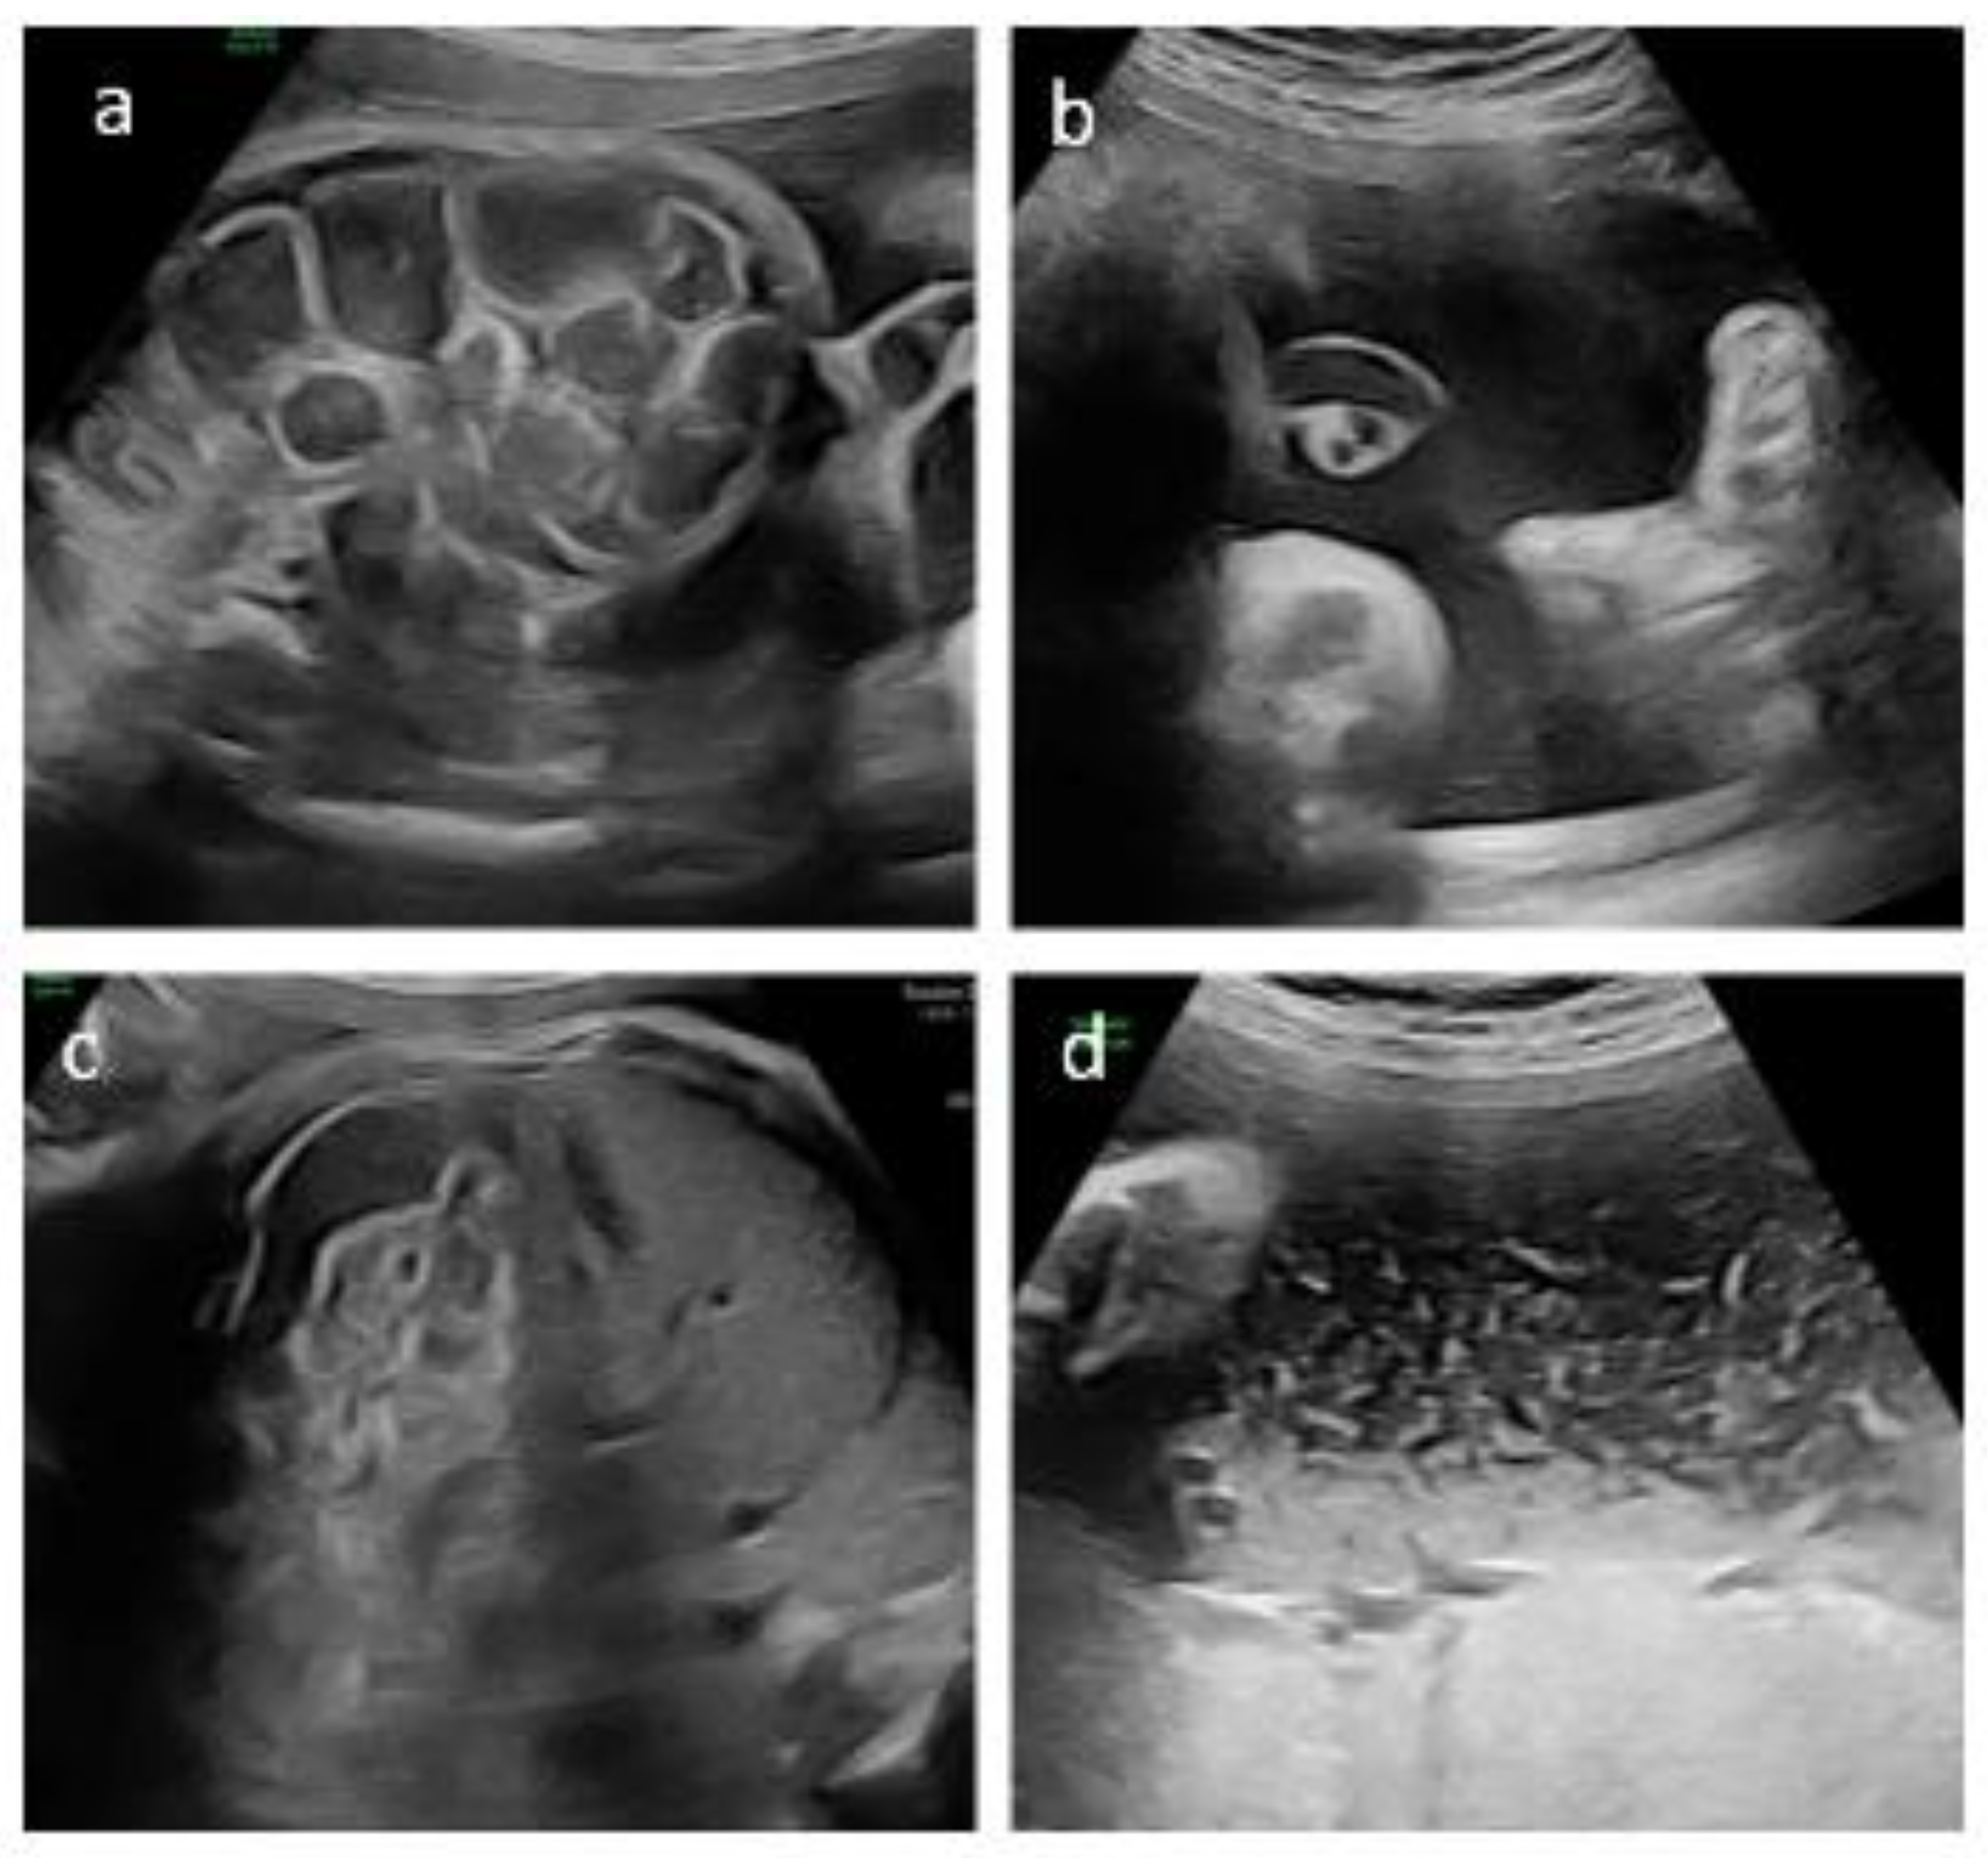

We report the case of a 36-year-old primigravida who conceived spontaneously. First trimester aneuploidy and mid trimester structural screening were unremarkable. During the third trimester, diffuse dilatation of the fetal bowel loops was detected. Subsequent parental genetic screening revealed that both parents were heterozygous carriers of the F508del mutation in the CFTR gene. The couple declined invasive prenatal testing at that time. The patient was referred to our maternal-fetal medicine unit at 33+0 weeks of gestation. Diffuse dilation of the fetal bowel loops was confirmed, with the largest loop measuring 18.2 mm in diameter and a wall thickness of 1.7 mm, with preserved peristalsis (Figure 1).

A multidisciplinary team (CF specialists, maternal–fetal medicine experts, pediatric surgeons and clinical ethicists) was rapidly convened to evaluate the initiation of maternal ETI therapy despite the absence of regulatory approval for fetal indications [8]. Following extensive discussion, compassionate off-label prenatal treatment was approved, supported by hospital institution and a local CF patient association and grounded in the ethical principle of “primum non nocere”, given the absence of reported maternal or fetal toxicities with ETI therapy. Before the medication was dispensed, follow-up US demonstrated new onset polyhydramnios, prompting amnioreduction and fetal CFTR analysis. Genetic testing confirmed fetal CF with homozygosity F508del mutation. After informed parental consent and formal ethics committee approval, maternal ETI therapy was started at 33 weeks of gestation using the standard adult dosing regimen. The mother was clinically healthy. The aim of therapy was to improve the fetal condition, specifically to reduce or resolve fetal bowel dilatation due to presumed MI. Treatment was well tolerated, and serial laboratory monitoring showed no clinically significant abnormalities. No maternal adverse effects were observed during the entire treatment period. Between 34+0 and 36+0 weeks’ gestation, serial US demonstrated progressive stabilization and improvement of both intestinal findings and amniotic fluid volume. At 34+0 weeks, the largest bowel loop measured 15 mm with thin walls and preserved peristalsis, amniotic fluid was normal, and fetal growth appropriate for gestational age. By 36+0 weeks, bowel dilatation decreased to 13 mm with increased wall thickness but preserved peristalsis, and amniotic fluid was at the upper limit of normal (Figure 1).

Figure 1. Ultrasound findings of the bowel and amniotic fluid before (a,b) and after (c,d) treatment with ETI. At 33 weeks’ gestation, diffuse bowel dilation with increased wall thickness (1.7 mm) and poorly echogenic amniotic fluid are observed (a,b). At 36 weeks’ gestation, reduced bowel caliber with persistent wall thickening and markedly echogenic amniotic fluid consistent with meconium are observed (c,d).